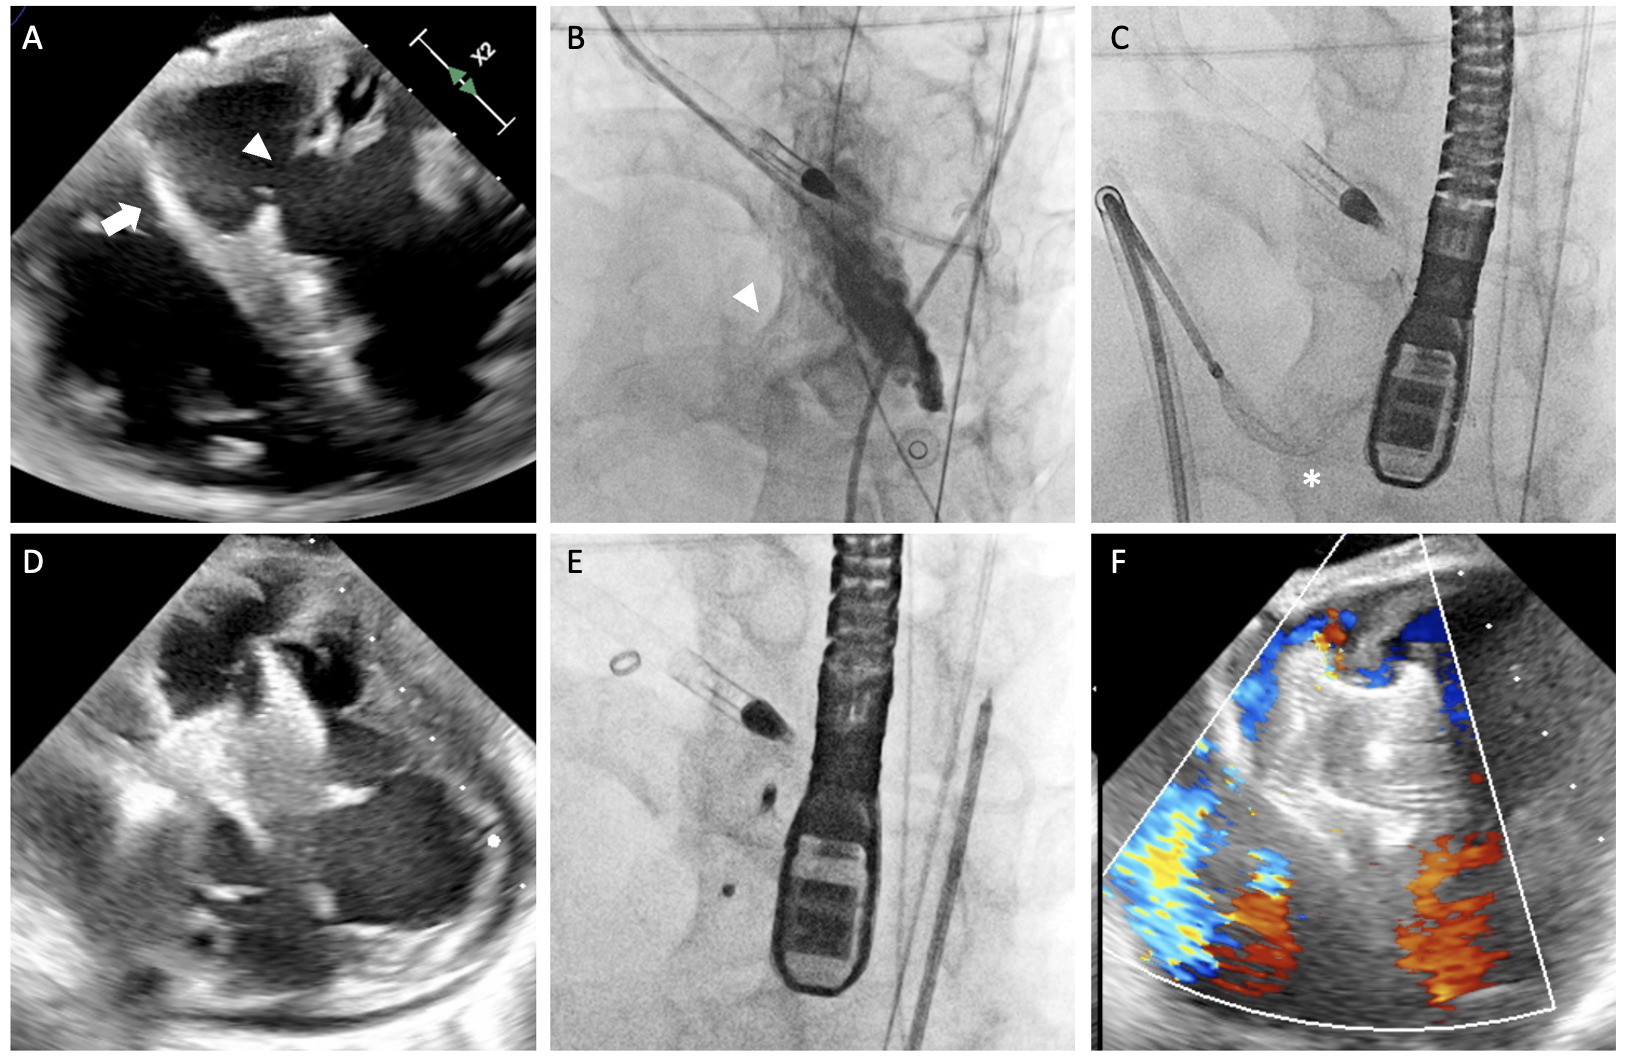

Transesophageal echocardiography (TEE) and a left ventriculogram revealed a 15-mm VSR in the inferoseptal region. There was a thick moderator band next to the right ventricular (RV) exit site (Figure A and B). The VSR was crossed with a Judkins Right catheter and a Glidewire (Terumo) was snared in the left pulmonary artery, forming an arterial-venous loop. The Glidewire was then exchanged for an Amplatz Super Stiff guidewire (Boston Scientific) for antegrade passage of the 10-French 45° curved delivery sheath from the right femoral vein. A 22-mm Amplatzer Post-infarct Muscular Ventricular Septal Defect Occluder (Abbott) was delivered by antegrade approach. However, after left disc deployment, there was a cobra-neck deformity of the right disc due to entanglement between the device and the moderator band (Figure C and D).

Therefore, it was decided to deploy the same device by retrograde approach. Proper formation of the right disc was achieved despite some interaction with the moderator band. With further pulling, the right disc was freed from the moderator band and the VSR was successfully closed with minimal residual flow (Figure E and F, Video). The device remained stable in follow-up echocardiography and chest x-ray. Unfortunately, the patient succumbed to multiorgan dysfunction 5 days later.